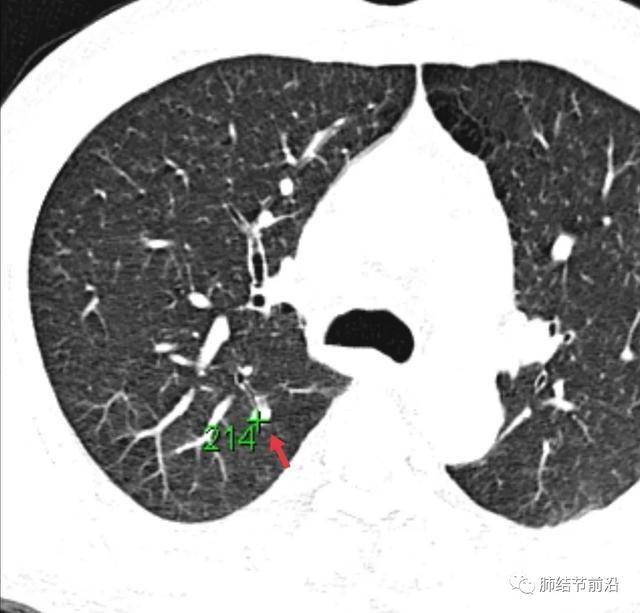

有研究统计,肺结节的ct值超过167,基本考虑慢性炎症纤维化.